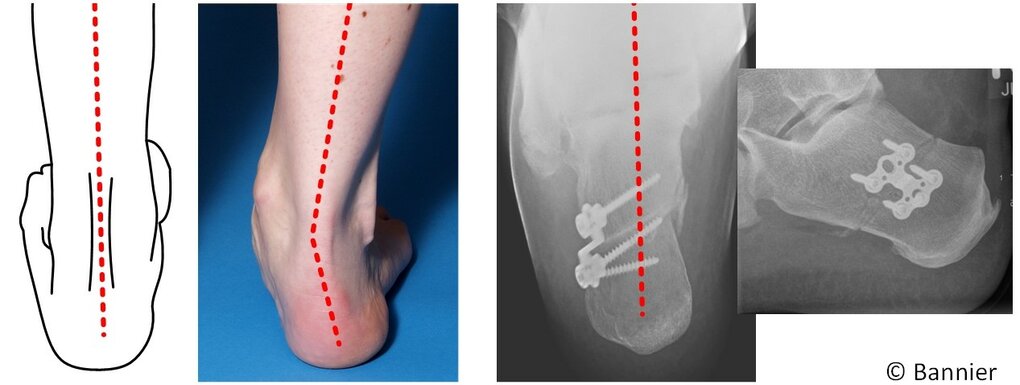

Abb. v.l.n.r.:

Skizze: Ein gesunder linker Fuß, bei dem Unterschenkel und Ferse in einer Linie stehen.

Foto: Ein rechter Fuß in Knickstellung. Die Achsen von Unterschenkel und Ferse bilden einen Knick.

Röntgenbild 1: Die operative Korrektur umfasste in diesem Fall die Umstellung des Fersenbeines und Fixierung mittels einer Platte und 4 Schrauben. DIe gestrichelte rote Linie zeigt die korrigierte Achse zwischen Schien- und Fersenbein.

Röntgenbild 2: Der gleiche Fuß von der Seite geröngt.